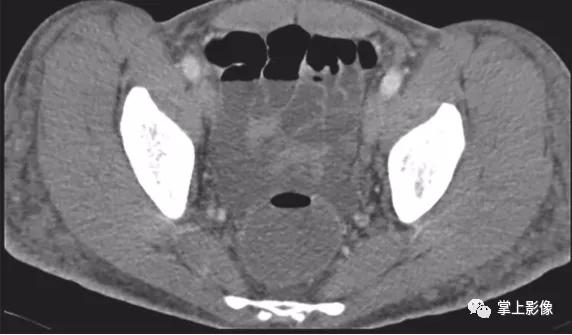

54岁男性肾移植后的移植后淋巴组织增生性疾病。轴位CT显示多个脐上腹壁结节(箭头)